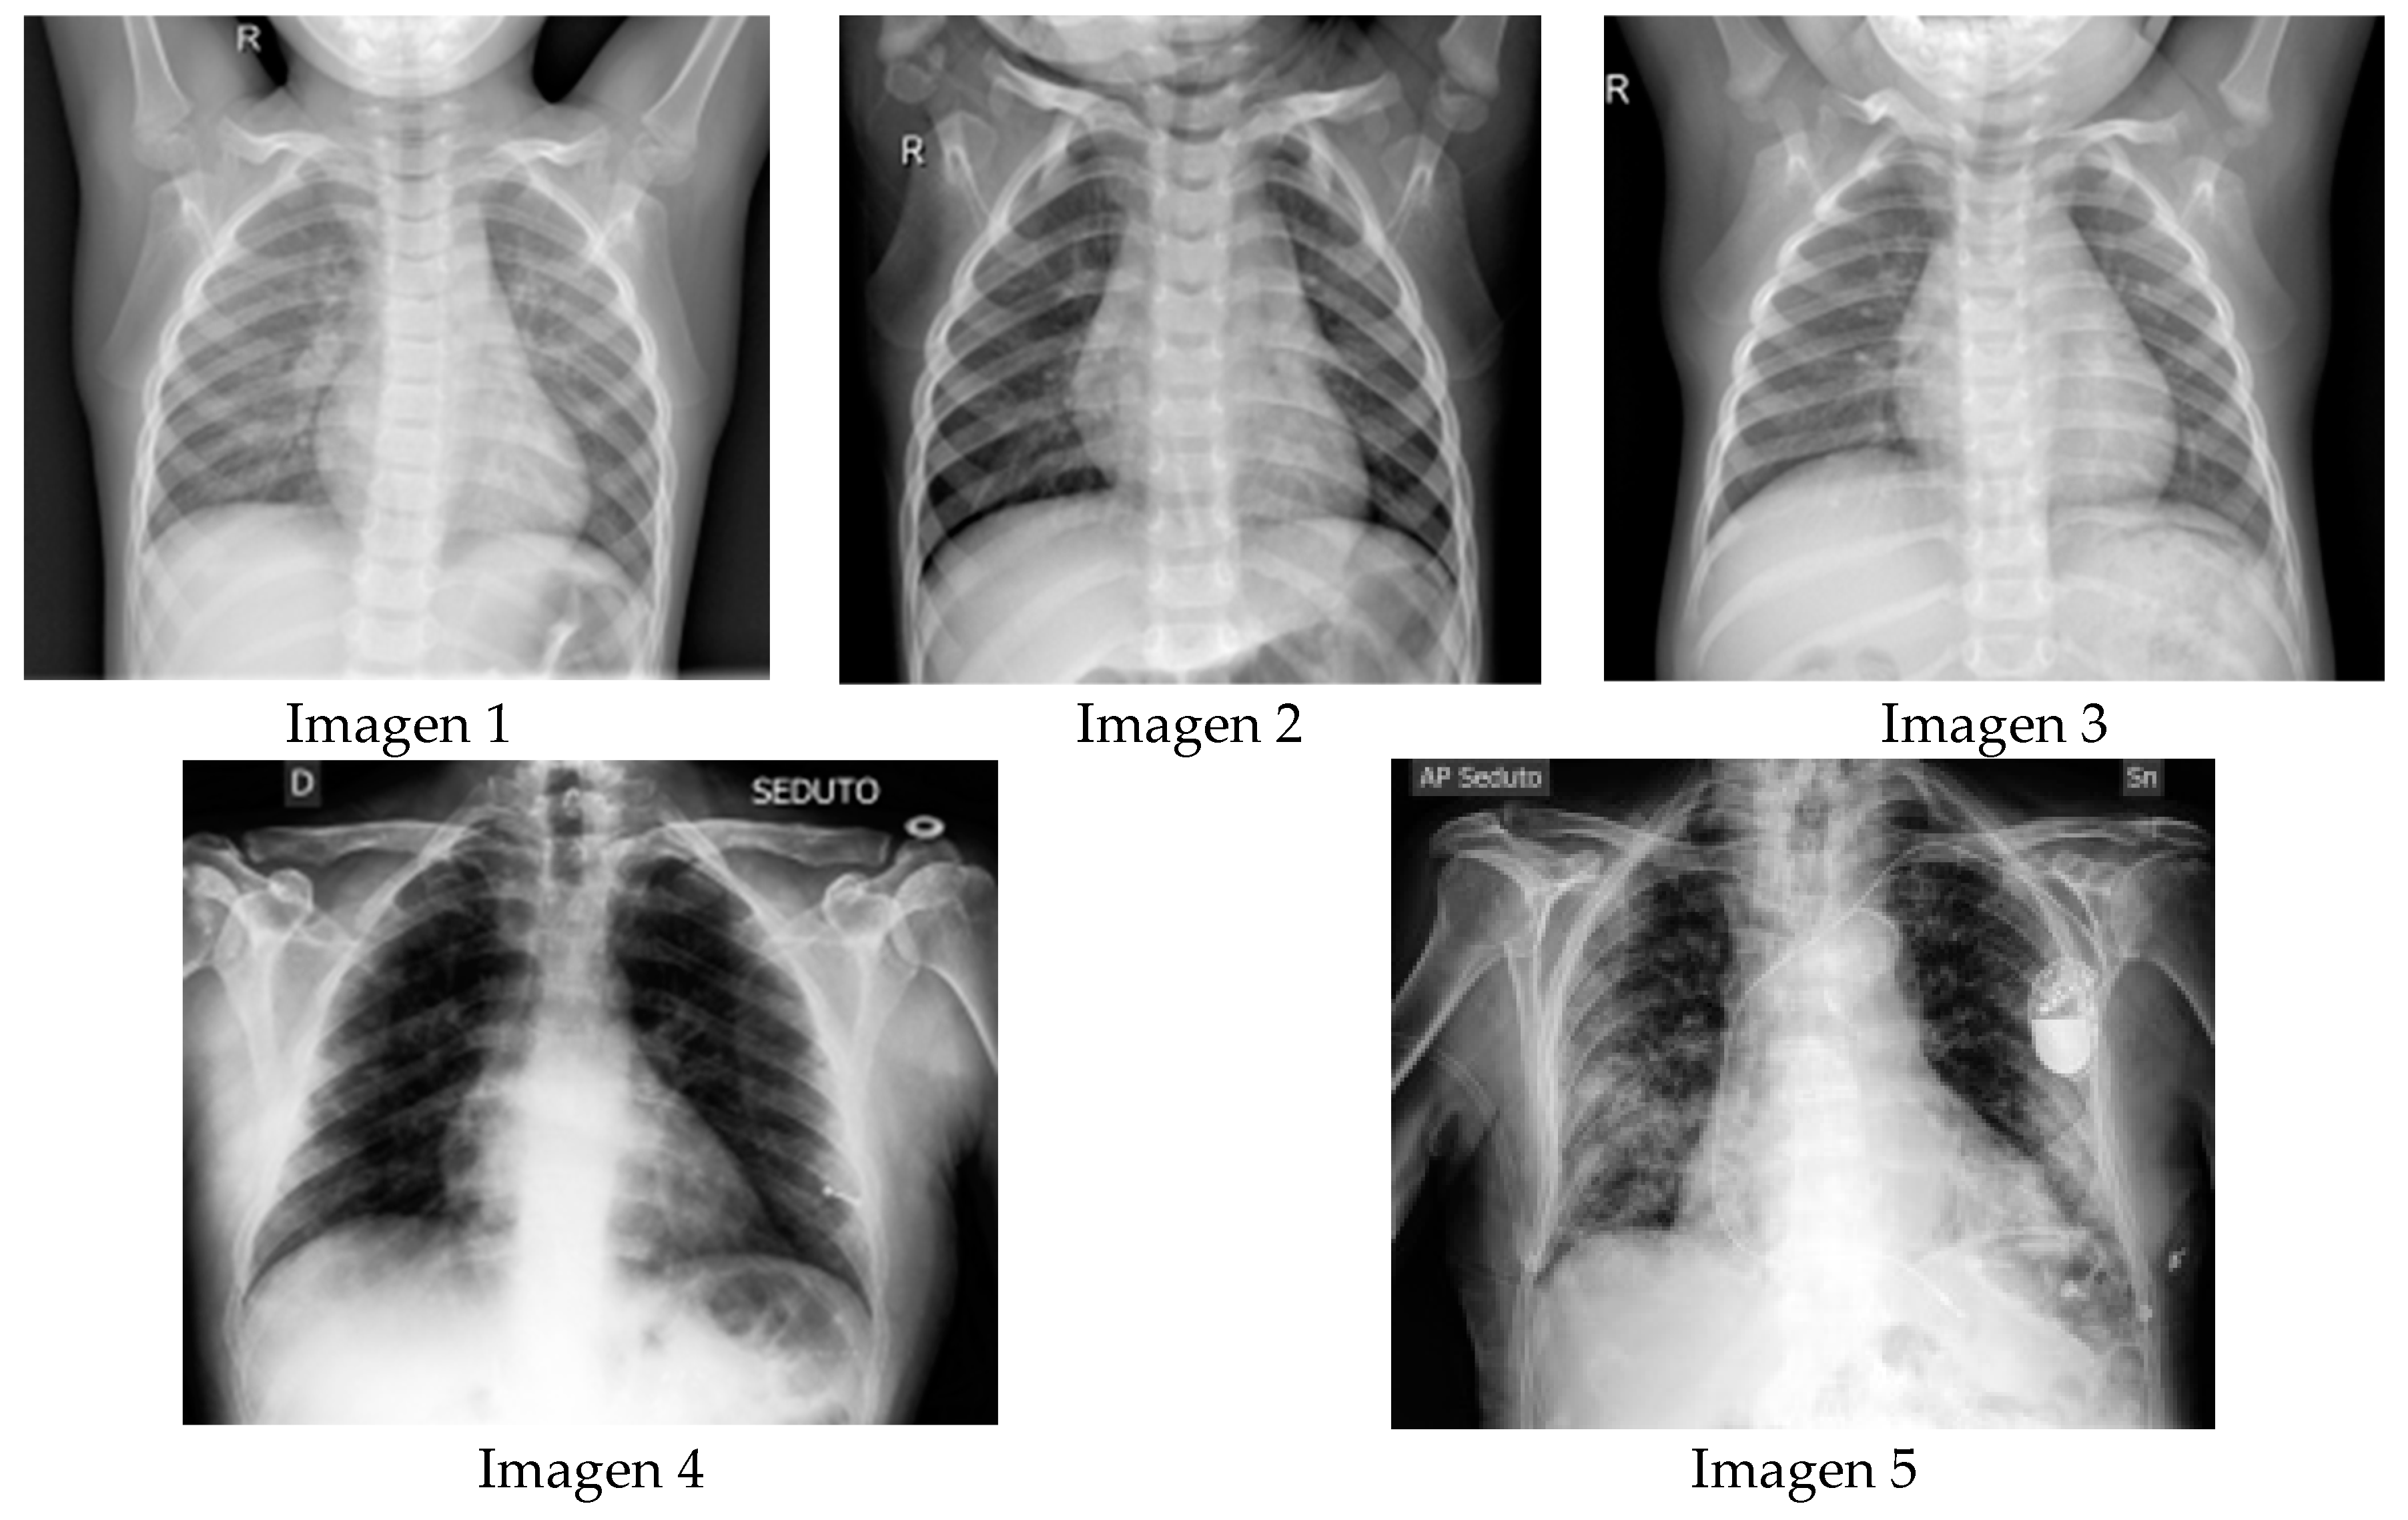

| Image 1 | Image 2 | Image 3 | Image 4 | Image 5 | ||